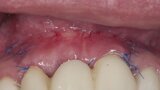

Biomodulacja laserem Nd:YAG z użyciem głowicy Genova®